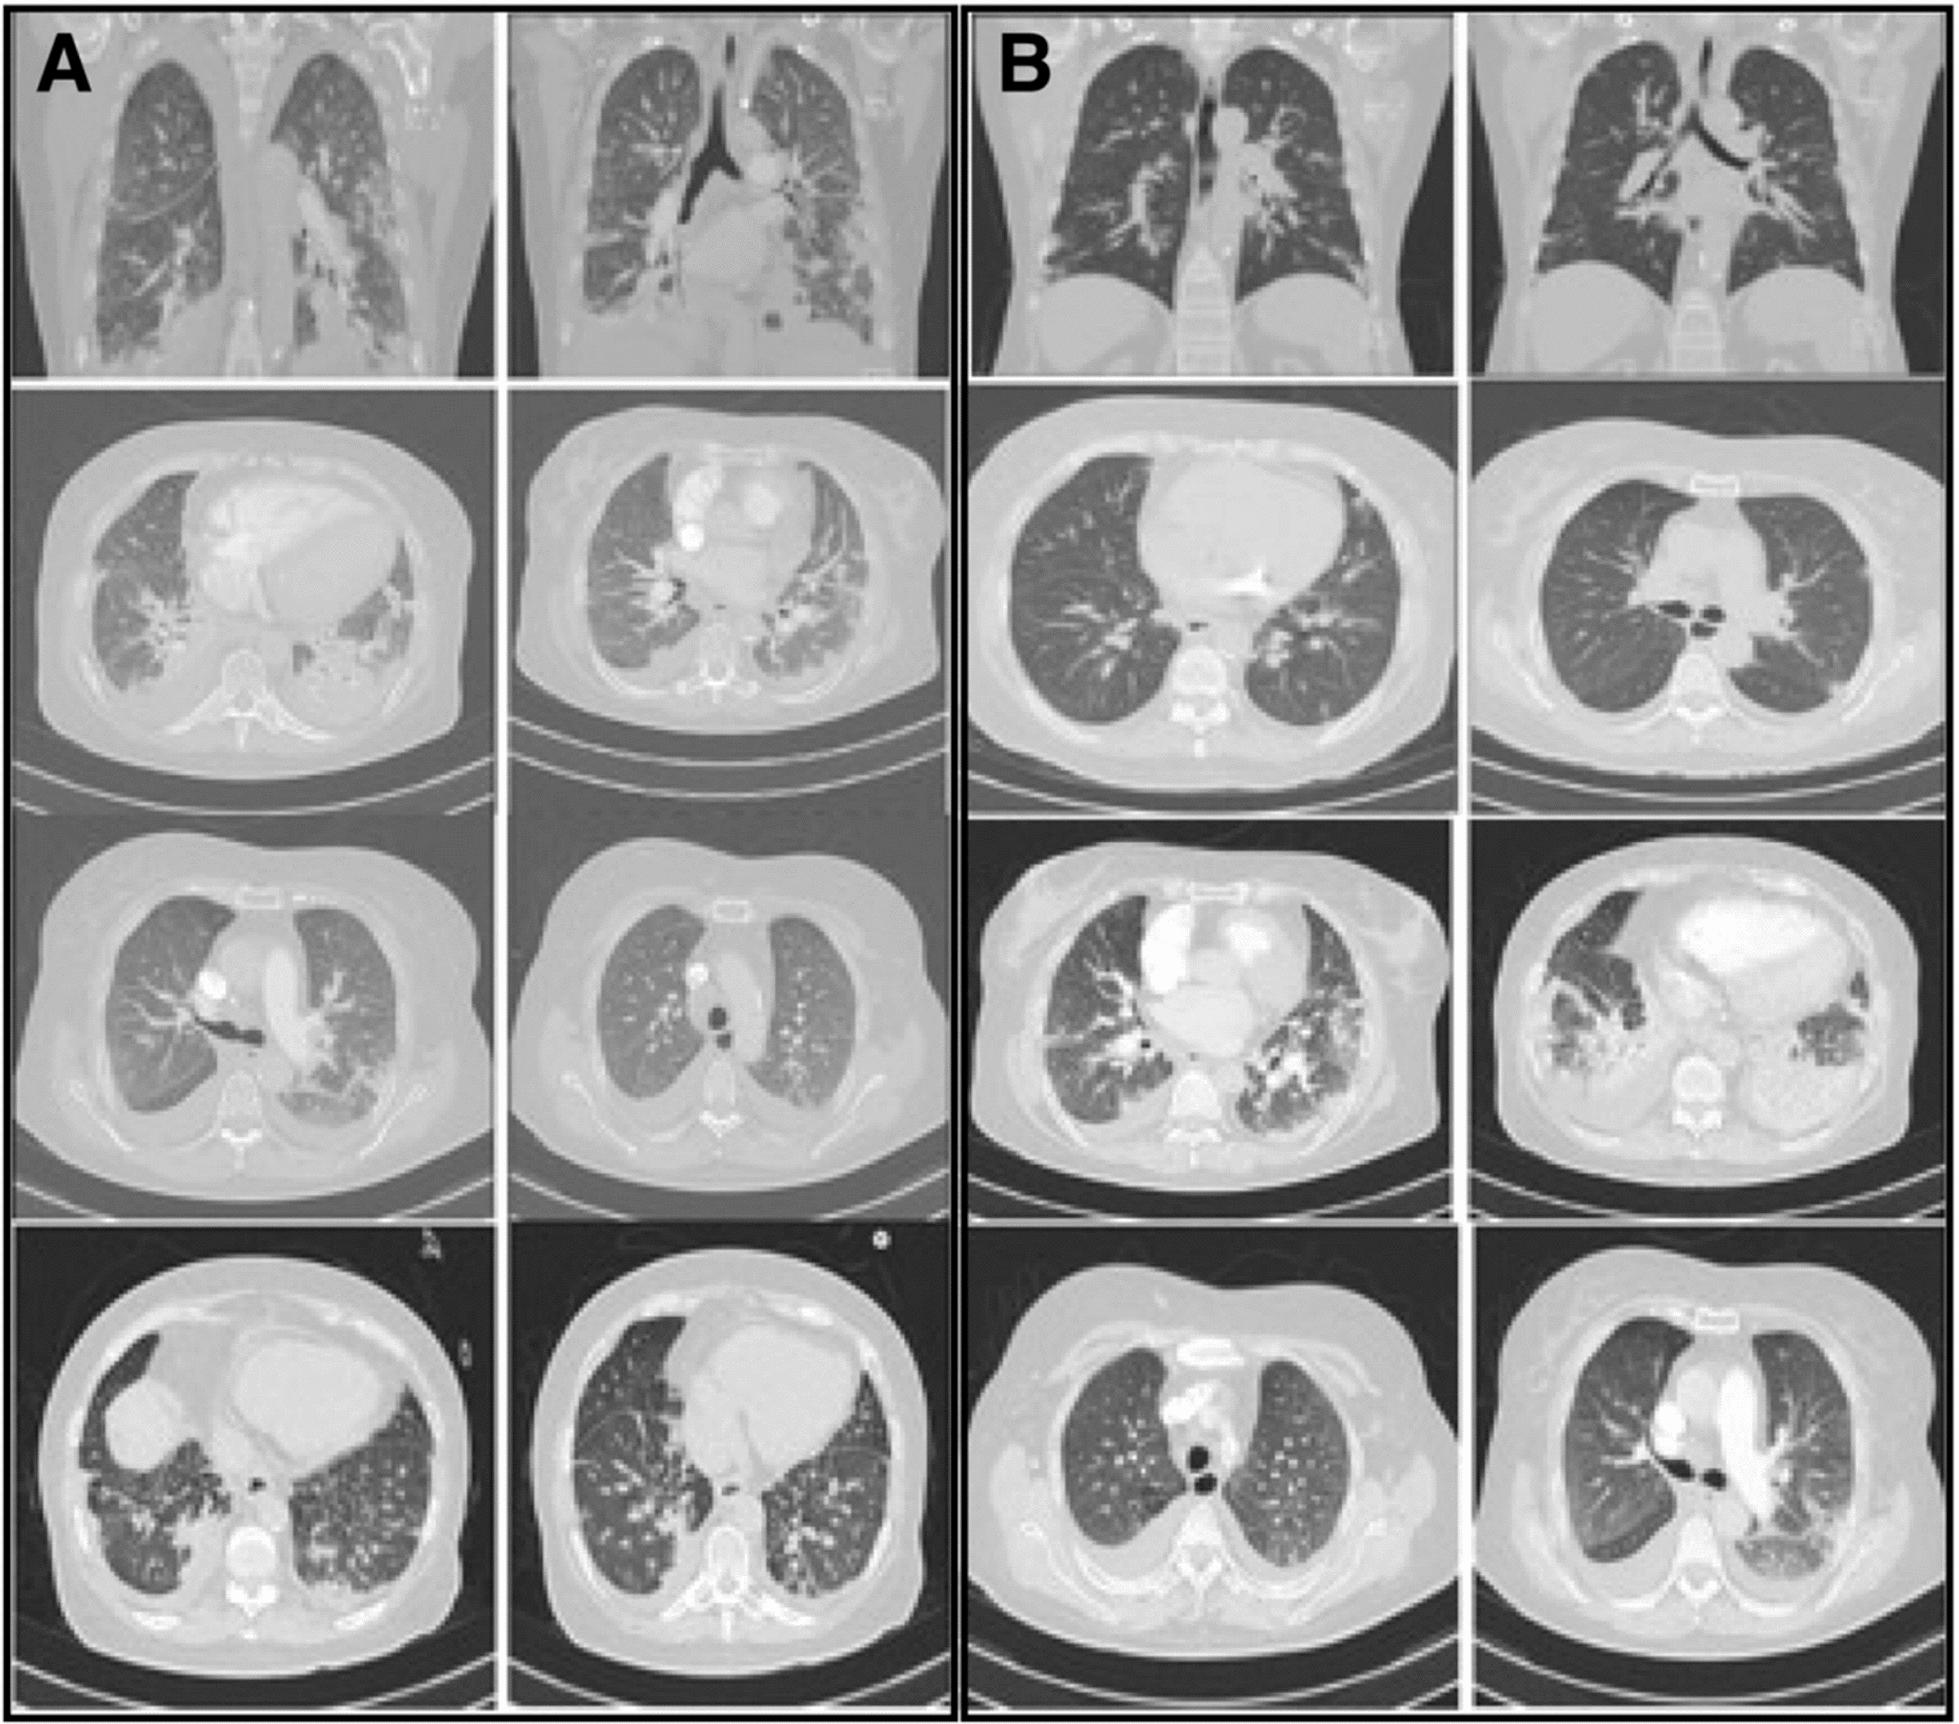

We report three cases involving mixed-race Colombian female patients aged 58, 35, and 63 years who experienced multiple episodes of coronavirus disease 2019 infection, with the most recent episode progressing to critical illness. These cases were characterized by relapses or persistent infections, and genomic analyses consistently identified the Omicron severe acute respiratory syndrome coronavirus 2 lineage as the causative variant. Notably, individuals with underlying immunosuppressive conditions developed severe acute respiratory syndrome coronavirus 2 infections that were more severe, leading to fatal outcomes that included acute respiratory distress syndrome, multiorgan dysfunction, and death. In contrast, one vaccinated patient with significant comorbidities exhibited persistent critical coronavirus disease 2019 but responded positively to treatment with tocilizumab.

我们报告了三例涉及不同种族的哥伦比亚女性患者的病例,年龄分别为58岁、35岁和63岁,她们经历了多次2019年冠状病毒病感染,最近一次感染进展为危重症。这些病例的特征是复发或持续感染,基因组分析一致确定奥密克戎严重急性呼吸综合征冠状病毒2谱系为致病变体。值得注意的是,患有潜在免疫抑制疾病的个体发生的严重急性呼吸综合征冠状病毒2感染更为严重,导致包括急性呼吸窘迫综合征、多器官功能障碍和死亡在内的致命后果。相比之下,一名患有严重合并症的接种疫苗患者表现出持续的2019年冠状病毒病危重症,但对托珠单抗治疗反应良好。